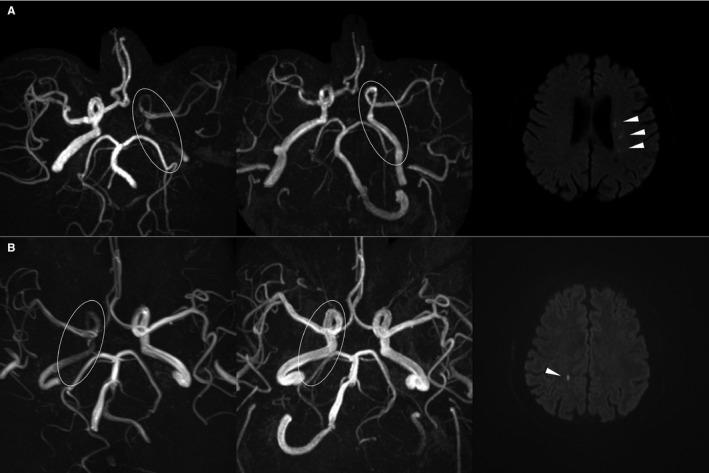

We assessed 304 consecutive carotid endarterectomy cases treated over 3 years. Included cases had both preoperative and postoperative intracranial 3-dimensional time-of-flight magnetic resonance angiography, of which signal intensities are flow dependent, and postoperative diffusion-weighted imaging (≤3 days following carotid endarterectomy). Preoperative TILs in the ipsilateral intracranial arteries were evaluated by the presence of nonexclusive components: focal stenosis (>50%), diffuse stenosis (>50%), and decreased signal intensities (>50%). The components showing postoperative normalization were considered hemodynamic. TILs with hemodynamic components were defined as hemodynamic TILs, while others as consistent TILs. Baseline characteristics and postoperative outcomes were analyzed among 3 groups: no TILs, consistent TILs, and hemodynamic TILs. Preoperative TILs were identified in 104 (34.2%) cases; 54 (17.8%) had hemodynamic components. Diffuse stenosis and decreased signal intensities were usually reversed postoperatively. Patients with hemodynamic TILs tended to have severe proximal carotid stenosis and recent strokes (≤14 days). For the outcome, hemodynamic TILs were independently associated with the advent of postoperative ischemic lesions on diffusion-weighted imaging (odds ratio: 2.50; 95% CI, 1.20-5.20).

我们评估了3年内连续治疗的304例颈动脉内膜切除术病例。纳入的病例术前行颅内三维时间飞跃磁共振血管造影(其信号强度依赖血流),术后行弥散加权成像(颈动脉内膜切除术后≤3天)。通过以下非排他性成分评估同侧颅内动脉术前TILs:局灶性狭窄(>50%)、弥漫性狭窄(>50%)和信号强度降低(>50%)。术后恢复正常的成分被视为血流动力学成分。具有血流动力学成分的TILs被定义为血流动力学TILs,其他的为持续性TILs。分析了三组(无TILs、持续性TILs和血流动力学TILs)的基线特征和术后结局。104例(34.2%)病例术前发现有TILs;54例(17.8%)有血流动力学成分。弥漫性狭窄和信号强度降低术后通常会逆转。有血流动力学TILs的患者往往有严重的近端颈动脉狭窄和近期卒中(≤14天)。就结局而言,血流动力学TILs与弥散加权成像上术后缺血性病变的出现独立相关(比值比:2.50;95%可信区间,1.20 - 5.20)。